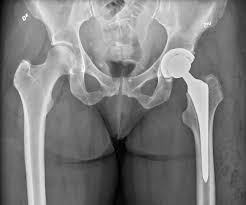

Preoperative preparation plays a vital role in the success of hip replacement surgery. Therefore, patients undergo X-rays, blood tests, and medical fitness assessments before surgery. At Varunam Hospital, detailed planning ensures accurate implant selection and surgical approach. Moreover, Dr. Utsav Agrawal emphasizes patient education regarding the procedure, risks, and recovery expectations. As a result, patients enter surgery prepared, informed, and confident.

Hip replacement surgery involves removing the damaged joint and replacing it with a prosthetic implant to restore movement. Therefore, precision and surgical expertise are essential for successful outcomes. At Varunam Hospital, surgeries are conducted following standardized orthopedic protocols under the clinical leadership of Dr. Utsav Agrawal. Moreover, careful tissue handling and implant positioning reduce complications and improve joint function. As a result, patients experience effective pain relief and improved mobility after surgery.